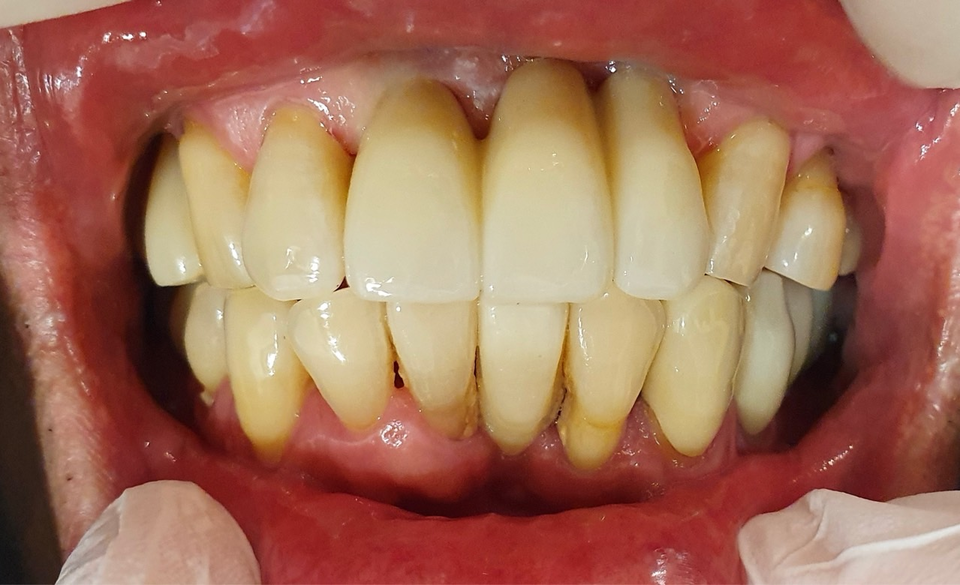

필자는 20년 넘게 각종 임플란트를 시술했고 임플란트의 안전성과 더불어 디지털 시대의 보철의 편의성을 꼼꼼히 따져 Bright implant를 시도하게 됐다.

수술은 간단명료하고 초기고정이 좋고 디지털 스캔이 잘되며 제작의 오차가 없고 내구성 예후가 매우 좋았다.